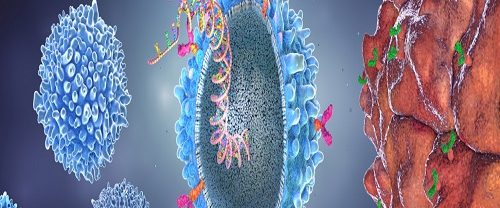

Eksozom Nedir ve Ne İşe Yarar? Eksozomlar, hücrelerin dışına salgıladığı küçük keseciklerdir. Bu kesecikler, hücre içerisinde bulunan çeşitli biyomoleküllerin dışarıya aktarılmasını sağlar. Hücreler arasında iletişim ve bilgi transferi için önemli bir rol oynar. Genellikle hücre zarı ile çevrili olan küçük veziküllerdir. İçerdikleri biyomoleküller hedef hücrelere taşınarak çeşitli etkiler gösterebilir. Proteinler, nükleik asitler (RNA ve DNA),…